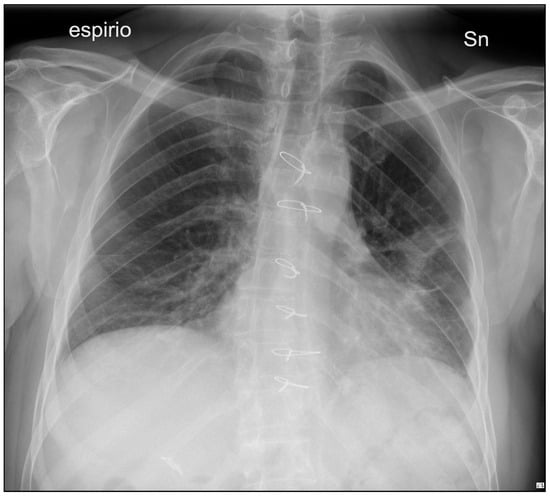

A 53-year-old man with a self-inflicted gunshot wound to the chest was admitted to our Emergency Department. He was hemodynamically unstable, with low values of blood pressure (70/40 mmHg), tachycardia (120 beats per minute) and hypoxemia (peripheral oxygen saturation 80%). Medical examination revealed a 12 mm, round, bullet entry wound at the 3rd intercostal space on the left midclavicular line. An emergency bedside ultrasonography (Point of Care Ultrasound—POCUS) revealed left pleural and pericardial effusion. He was intubated, transfused with one blood bag of iso rhesus, and ev fluid instillation and vasoconstrictor support were started. A chest film showed massive left-sided pleural effusion (Figure 1). Blood samples were as following: hemoglobin concentration 10.6 g/dL, Platelet count 176,000/mmc, Prothrombin Time (PT) 53%, Partial Thromboplastin Time (PTT) 27 s, INR 1.42. His past medical history was characterized by systemic hypertension, treated with Calcium Antagonist 10 mg/die and Acetylcholinesterase inhibitor 10 mg/die. Due to unresponsive hemodynamic instability, the patient was immediately transferred to the operating room by the cardiac and thoracic surgery teams without any further instrumental examination.

Figure 1. Admission chest film showing massive left hemothorax.